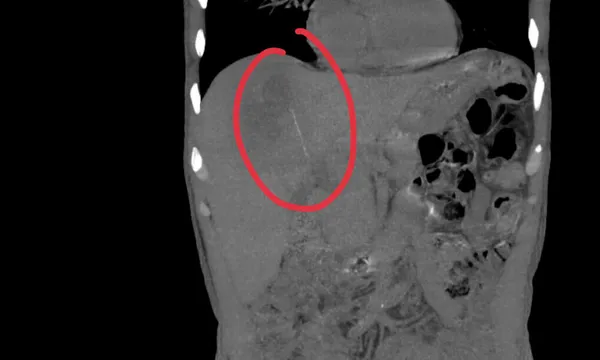

Khi tiến hành siêu âm kỹ hơn, ê kíp phát hiện một dị vật cản quang xuyên trong nhu mô gan, chiều dài ước tính khoảng 6-7cm. Ngay sau đó, bệnh nhân được chỉ định chụp cắt lớp vi tính (CT scan) ổ bụng.

Kết quả cho thấy có một dị vật dạng que dài nằm hoàn toàn trong nhu mô gan, kèo theo ổ áp xe sâu. Trước nguy cơ biến chứng nặng nếu không điều kịp thời, ê kíp khoa Nội tiêu hóa đã nhanh chóng hội chẩn cùng khoa Ngoại Gan Mật Tụy, thống nhất phương án phẫu thuật lấy dị vật, dẫn lưu ổ áp xe, kết hợp điều trị kháng sinh phù hợp.